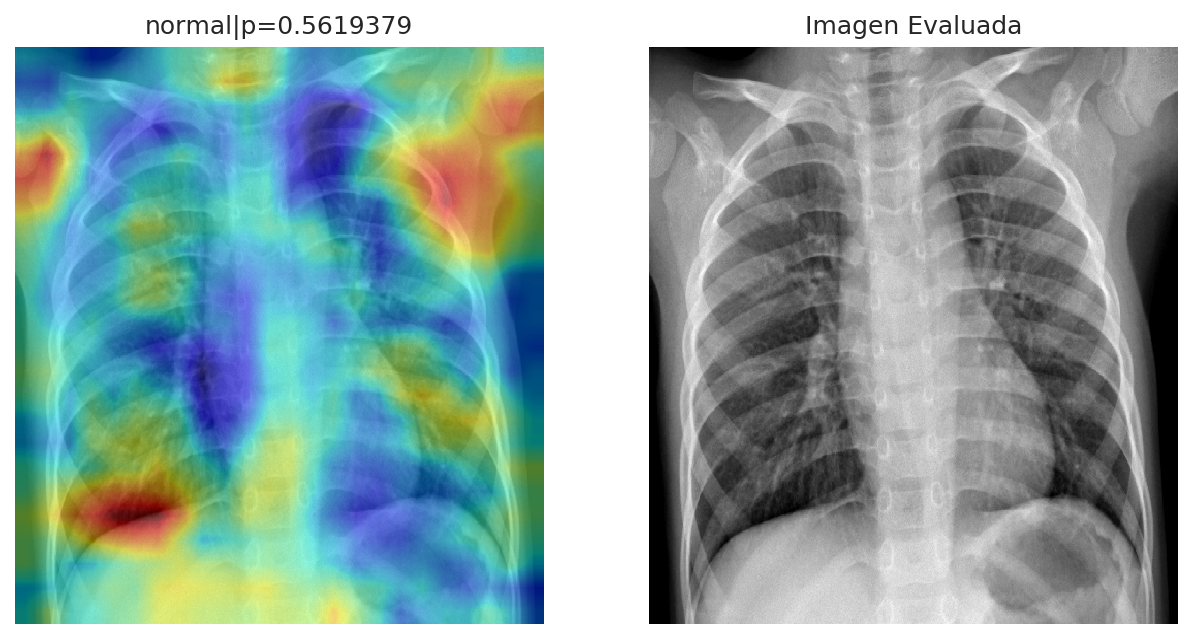

The diagnosis discards the presence of pneumonia in the patient. From the analysis, the patient present a normal state, with a 56.19% of confidence. Whereas the probability of having pneumonia is: 43.81%. The distribution for both states can be observed in the plot.

Diagnosis Summary: The patient do not shown signs of having pneumonia.

The zonal analysis shown, which areas from the image, where used to carry on the diagnosis. This represent the zones where the algorithm detect pneumonia or a normal state. The cold colors, represent the zones, which have a probability of having a normal state, whereas the warm colors represent the probability of pneumonia in such zones. This information is intended to bring support as evidence about the diagnosis. Since this application is under development, some zones mark areas out of the main image. This will be improved in the next iterations. To see the analysis in more detail, click on the image to zoom in.